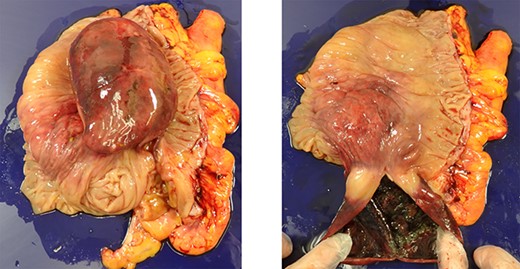

A cystic lesion originated from cecum, with a necrotic discoloration of the cyst wall. When the cyst was incised, it contained a brown malodorous liquid inside, and the inner surface of the cyst was also necrotic (Fig. 3).

Excised specimen; there was a cystic lesion in the cecum, and the inner lumen of the cyst was necrotic.

Both the inside and outside of the wall were covered with colonic mucosa, and there was a muscularis mucosae in the submucosa, but no muscularis propria. Erosion was prominent on the mucosa inside the cyst, and diffusely severe inflammatory cell infiltration and edema were observed under the mucosa. There was no malignancy. From these findings, the lesion was diagnosed as intussusception of colon due to cecum cystic duplication.